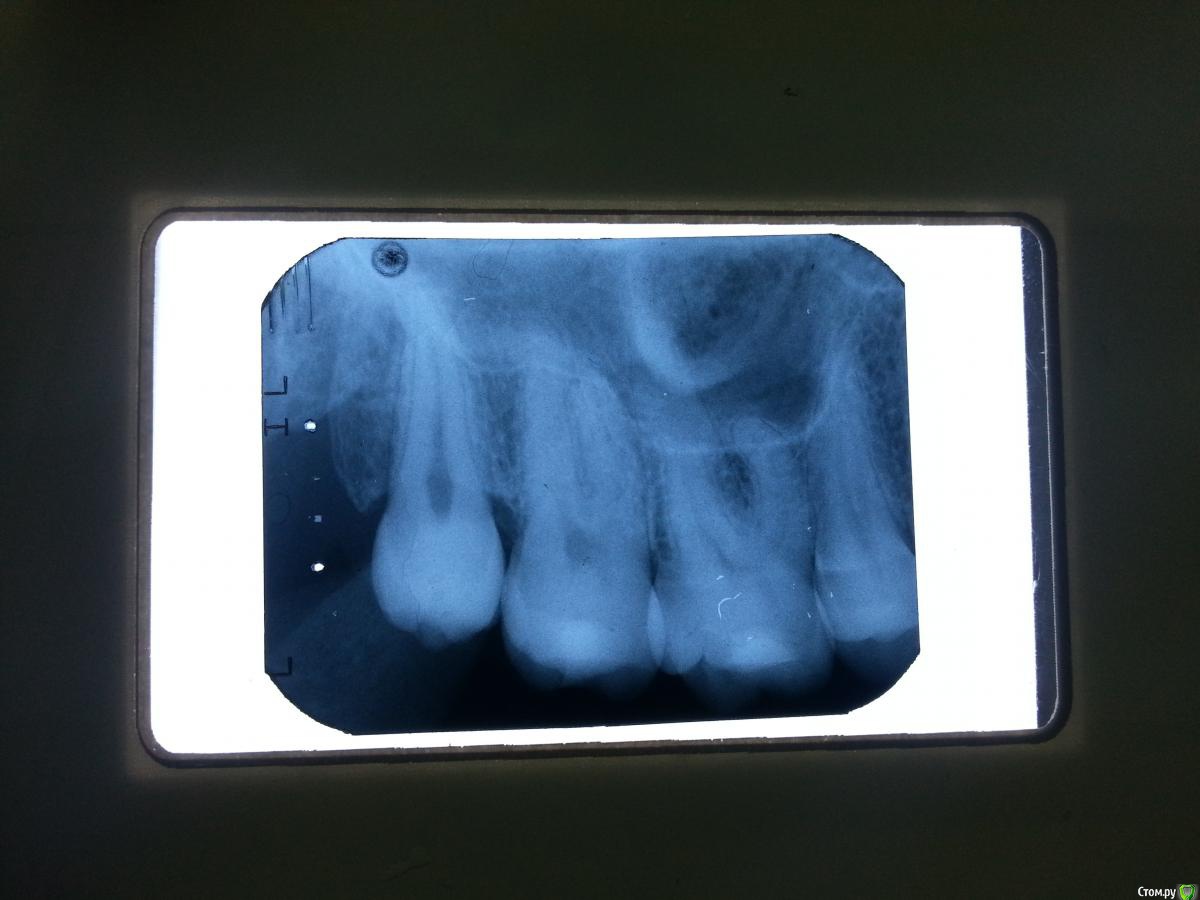

tarantino765 Опубликовано 11 ноября, 2015 Поделиться Опубликовано 11 ноября, 2015 жалобы на ноющие боли по ночам в области верхней челюсти справа, визуально все в норме, десна без изменений, перкуссия 16 зуба слегка болезненна, остальных в норме. Кто что думает? Ссылка на комментарий

tarantino765 Опубликовано 11 ноября, 2015 Автор Поделиться Опубликовано 11 ноября, 2015 вот снимок Ссылка на комментарий

DmitrySH Опубликовано 11 ноября, 2015 Поделиться Опубликовано 11 ноября, 2015 18, это трещина или артефакт на пленке? 1 Ссылка на комментарий

Елена Миллер Опубликовано 13 ноября, 2015 Поделиться Опубликовано 13 ноября, 2015 Вокруг 18 карман костный большой. Как там с гигиеной? Где-то есть пульпит, ищите. Может, нижние зубы с этой же стороны. Ссылка на комментарий

сирена Опубликовано 13 ноября, 2015 Поделиться Опубликовано 13 ноября, 2015 Вокруг 18 карман костный большой. Как там с гигиеной? Где-то есть пульпит, ищите. Может, нижние зубы с этой же стороны. Не такой большой,но может быть причиной подобных болей(как мне кажется).Невралгия - нет,ночные боли не характерны(это для Юляши55) Ссылка на комментарий

vse32 Опубликовано 25 ноября, 2015 Поделиться Опубликовано 25 ноября, 2015 вот снимокНасморка у пациента нет? Гайморит частенько дает такие боли.ЭОД можете сделать этих зубов?Невралгия себя ведет иначе.Ищите что-то более простое. Пульпит, гайморит, карманы.Пропальпируйте точки выхода тройничного, и в области щеки. Ссылка на комментарий

Kazankov.Egor Опубликовано 4 декабря, 2015 Поделиться Опубликовано 4 декабря, 2015 Кт, 16 похоже издох. 1 Ссылка на комментарий

tarantino765 Опубликовано 12 мая, 2016 Автор Поделиться Опубликовано 12 мая, 2016 tarantino765, чем закончилась история с пациентом? или ещё не закончилась? депульпировал 16, пациентка счастлива болей нет, а я живой)) 1 Ссылка на комментарий